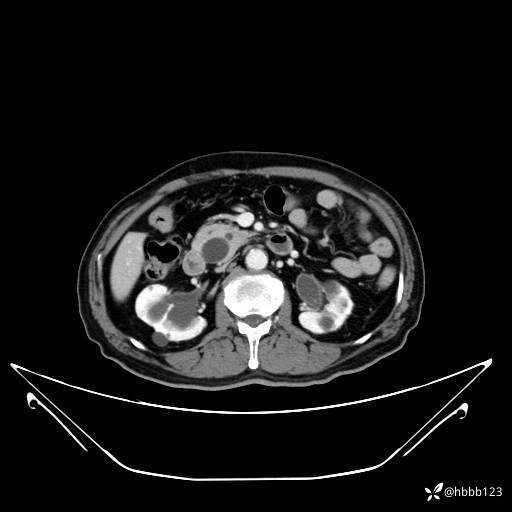

门脉期: